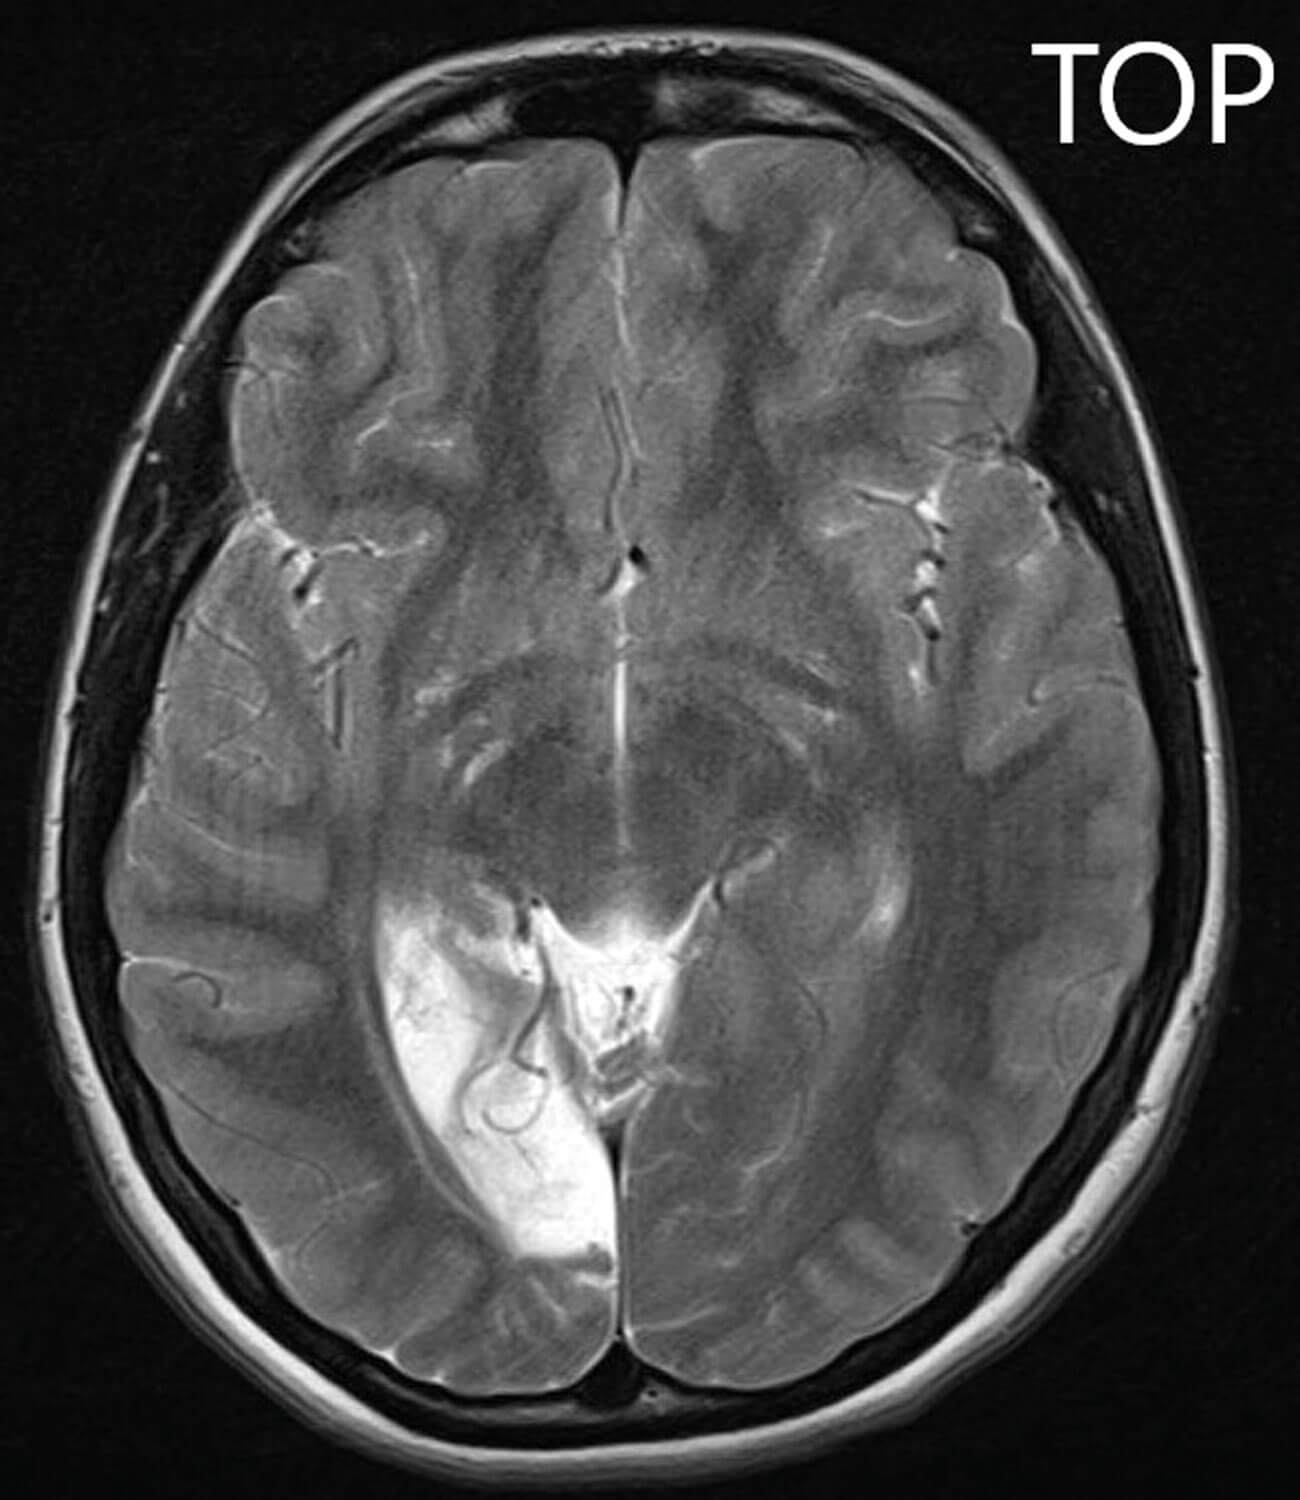

Figure 1: A T2-weighted MRI image of the patient’s brain,

demonstrating hyper-intensity in the right occipital lobe region.

The MRI scan (Figure 1) showed cortical and subcortical white matter volume loss in the right occipital lobe with secondary encephalomalacia, along with a focal area of cystic change within the right ventero-lateral thalamus. These findings led to a diagnosis of a chronic posterior cerebral artery territory infarct involving the right occipital lobe and posterior thalamus. She was commenced on Aspirin 75mg once-daily and admitted to a tertiary hospital for further review.